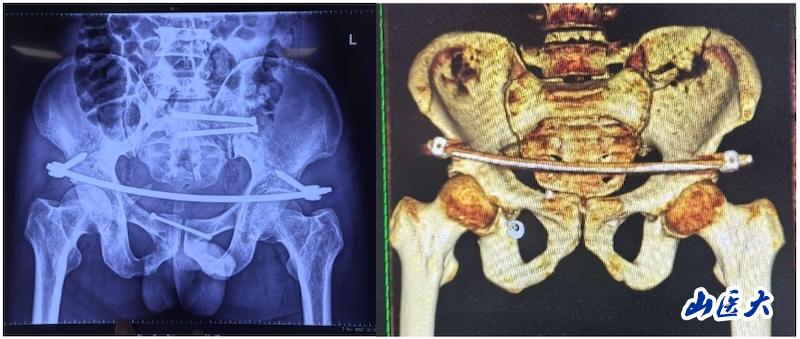

术后

据孙海钰介绍,骨盆髋臼骨折是一种严重的创伤,传统开放复位内固定术创伤大、恢复慢,而闭合复位则具有微创、出血少、恢复快等优点。随着医疗技术的不断进步,UCRT解锁复位技术结合天玑机器人及O-arm术中影像系统为骨盆骨折治疗提供了更加精准、微创的解决方案,该技术代表了当前骨盆骨折治疗的前沿方向。